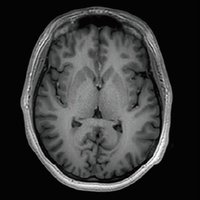

Der Vantage Galan 3T von Canon Medical Systems bietet Ihnen und Ihren Patienten eine neuartige Erfahrung in der Magnetresonanztomographie. Der Vantage Galan 3T legt sein Augenmerk auf das positive Patientenerlebnis, eine hohe Bildqualität und einfache klinische Arbeitsabläufe.

KI-optimiertes Arbeiten und modernste 3T-Technologie machen den Vantage Galan 3T von Canon Medical aus. Canons KI-Anwendung AiCE, kurz für Advanced intelligent Clear-Imagequality Engine, entfernt intelligent das Rauschen und führt zu einer Verbesserung des SNR (Signal-Rausch-Verhältnis). Mit Hilfe der Deep Learning Technologie gelingen besonders klare und deutliche Bilder. Insgesamt ermöglicht die KI-Unterstützung des Vantage Galan 3T somit nicht nur eine höhere Auflösung der Bilder, sondern verkürzt in vielen Fällen auch die Aufnahmezeit.